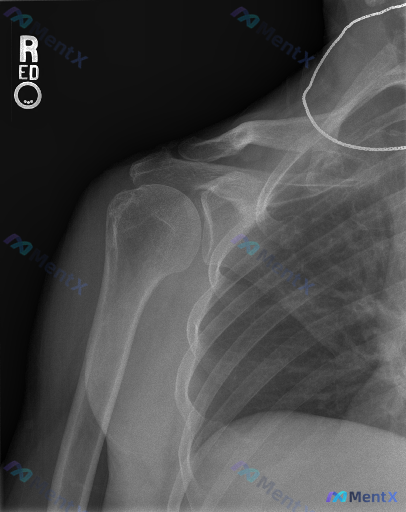

整理到一份右肩关节正位X光片的资料,先抛出来和大家讨论下读片和后续思路。 先看影像的客观表现: - 肱骨近端、锁骨远端、肩胛骨各部位骨皮质连续,未见明确骨折线、脱位或半脱位 - 盂肱关节、肩锁关节间隙基本正常,对合可 - 肩峰下间隙等未见明显狭窄或异常钙化 - 无明显退行性骨关节炎或骨质密度异常 影...